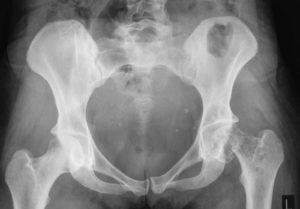

Диагноз ставится на основании рентгенографического исследования. Если картина повреждения и особенности расположения отломков недостаточно ясны, то проводится компьютерная томография тазобедренного сустава.

Этот метод позволяет получить послойное изображение проблемной области, точно оценить количество фрагментов кости, направление их смещения.